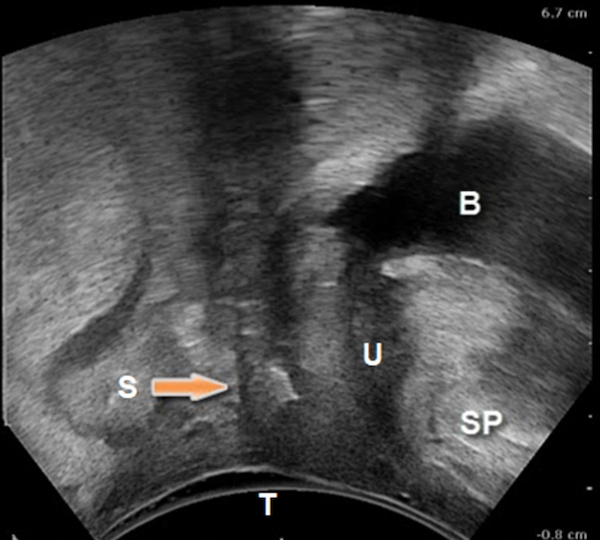

Figure 2

Endovaginal 180 degrees anterior compartment image in the midsagittal plane (transducer in the vagina scanning anteriorly): transobturator sling is seen to lie beneath proximal urethra B: Bladder; U: Urethra; S: Sling; UVJ: Urethrovesical junction; P: Symphysis pubis

The sling can be seen located mid-urethrally in Figure 1, underneath proximal urethra in Figure 2, and proximal to the urethrovesical junction in Figure 3, a year after surgery. Whether sling location impacts surgical outcome is a matter of controversy. Dietz et al (2004) concluded that variations in sling placement have little effect on symptom resolution and patient satisfaction in a study of 142 women whose outcomes were evaluated 5 weeks to 2.1 years following TVT sling surgery. Using transperineal ultrasound, the tape position in their study was found to vary from 30 mm above to 12.7 mm below the symphysis pubis at rest and between 15 mm above to 18.7 mm below the symphysis pubis on Valsalva. However, in an unmatched case-control study of 100 patients who underwent Monarc transobturator sling surgery, our group found that the sling location was significantly more proximal in those who had failed sling surgery when compared with those who had succeeded. In 90% of the patients in whom the sling had favorable outcomes, the sling was found to be located either beneath the āhigh pressure zoneā of mid-urethra or at the junction of the proximal and mid urethra (Hegde et al 2013).

The key differentiator in two studies is the fact that Dietz et al (2004) have used the symphysis pubis as the reference point for determining sling location; they measured the distance of the sling from the symphysis pubis. However, in our study we measured tape percentile (Hegde et al 2013), i.e., the distance of the midpoint of the sling from the urethrovesical junction divided by the urethral length. We found that when we determined sling location with respect to the urethral length, location had a significant impact on surgical outcomes.